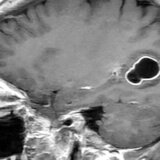

Neurohirurškinja Hari Prija Bandi istražujući misteriozne simptome jedne žene u jednoj australijskoj bolnici, kaže da je u mozgu žene našla crva od osam santimetara.

Bandi je obavila biopsiju kroz rupu na lobanji pacijenta u bolnici u Kanberi prošle godine i kleštima izvukla parazita.

Žena je primljena u bolnicu nakon što je tokom tri meseca doživela zaboravnost i pogoršanu depresiju. Skeniranje glave je pokazalo promene u njenom mozgu.

Senanaiake je očekivao da će biopsija mozga otkriti rak ili apsces.